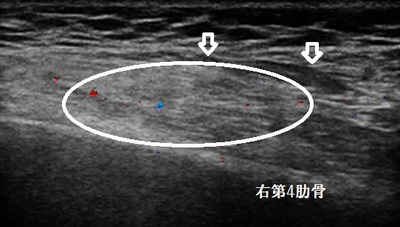

川越市若葉 男性 肋骨、胸の痛み 打撲

右第4肋骨 超音波長軸像

川越市若葉 80代男性。 肋骨、右胸の痛み、打撲。

【原因】

自転車で走行中、チェーンが外れて転倒しハンドルが右胸に強打してしまいました。痛くて暫くその場

から動けませんでした。1週間安静にしていましたが、右胸の痛みが消えず当院を受診されました。

超音波検査では肋骨に骨折はありませんでしたが、前鋸筋に打撲による筋損傷(画像の丸の囲み)と

内出血(画像の矢印)が認められました。

【治療】

受傷当初は肺を大きく膨らませるような深呼吸をすると患部に痛みがありましたが、現在は着替えや

腕を真上に挙げる動作で少し痛みます。患部を押すとまだ強い痛みがあります。

治療は患部内出血の吸収と前鋸筋損傷の修復を促進させる物理療法を行います。1週間ほどの通院加療で

早期治癒を目指します。